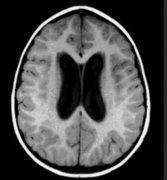

脑积水是神经外科常见的病症之一,是指颅内的脑脊液液体异常积聚,由于脑脊液的流动受阻或其产生与吸收不平衡引起,此外还有炎症反应、神经元损伤和室周轴突损害。 脑脊液生成...